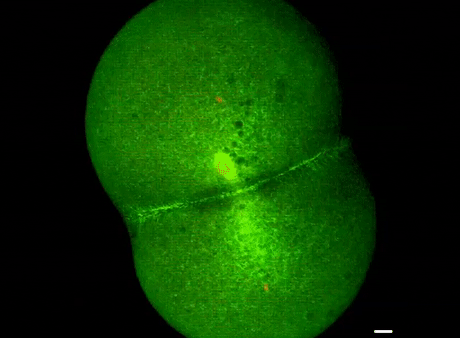

T細胞殺死癌細胞,視頻時長40分鐘

劍橋大學拍攝:T細胞(綠)衝向癌細胞(藍)

劍橋大學拍攝:T細胞(紅)纏住癌細胞(藍)搏鬥,綠色是T細胞釋放的毒素